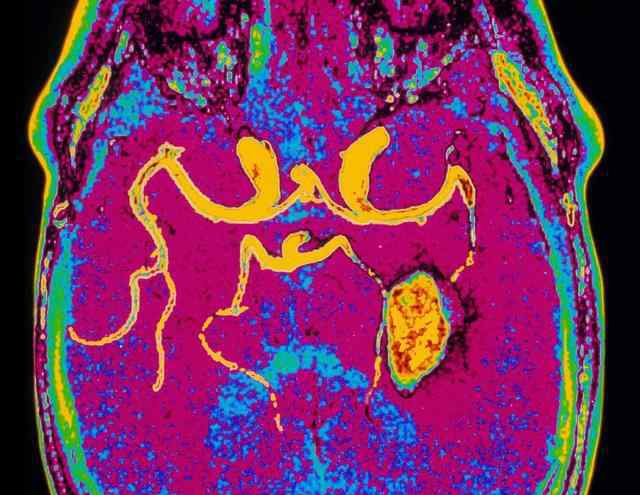

脑部CT检查的意义:脑部CT检查显示脑梗死病灶大小和位置的准确率为66.5% ~ 89.2%,早期脑出血的准确率为100%。因此,早期CT检查有助于脑出血的鉴别诊断和消除。这个很重要。脑出血和脑血栓在疾病早期的治疗有很大的不同。当脑梗死发病在24小时内,或梗死灶小于8 mm,或病变在脑干和小脑时,脑ct检查往往不能提供正确的诊断。如有必要,应在短时间内复查,以免延误治疗。